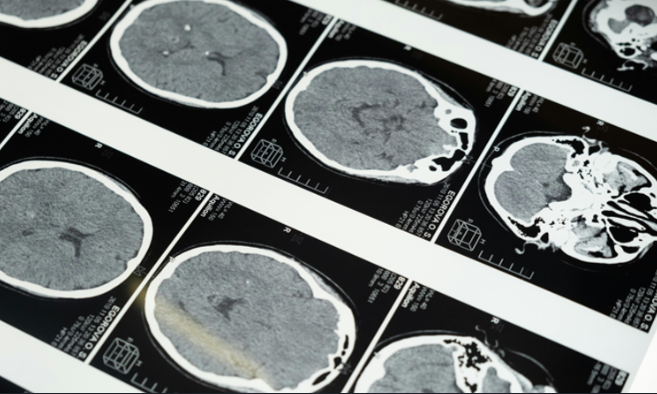

義大利波隆那神經科學研究所與多國研究團隊於2026年4月16日,在《考科藍系統性文獻回顧資料庫》(Cochrane Database of Systematic Reviews)發表一篇研究,彙整並分析7種藥物、共17篇臨床試驗研究、超過2萬名受試者的數據,探討新型抗類澱粉蛋白藥物對患者的幫助。研究結果指出,新型抗類澱粉蛋白藥物可以清除大腦中的類澱粉蛋白,但在減緩認知功能衰退和患者日常生活的幫助微乎其微,而且會增加腦水腫與腦出血等風險。台灣科技媒體中心邀請專家提供觀點,說明研究發現與限制。